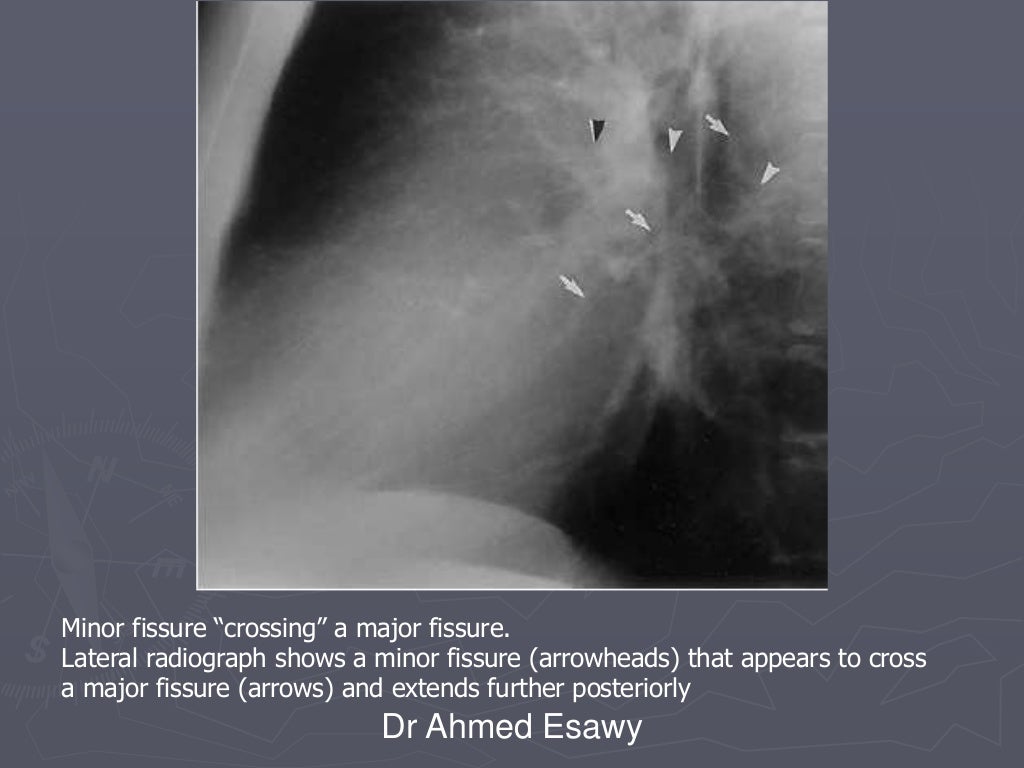

Linear lung density x ray Dr Ahmed Esawy

Linear lung density x ray Dr Ahmed Esawy What Is A Linear Density In The Lungs Lung densitometry, namely measurement of lung density, is based on the. These areas show increased density inside the lungs which could indicate. When it comes to any lung density, unfortunately, usually the first thought that creeps into the doctor's head is going to be some type of lung. In chest radiology, reticular and linear opacification refers to a broad subgroup. What Is A Linear Density In The Lungs.